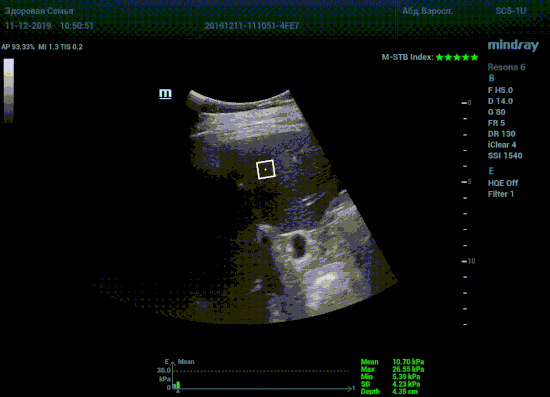

Определение плотности печени. Не ошибся ли оператор при измерении эластических свойств печени? Для оценки критериев качества предусмотрен индекс MBT, который покажет насколько «твердой» была рука оператора и двигалась ли печень. При MBT 5* рука тверда и показатели достоверны. Для оценки качества результатов используется IQR индекс, отображающий колебания показателей в точке измерения при расчете медианы. Показатели при IQR <30% считаются приемлемыми. Техника сканирования через межреберные промежутки требует размещение окна интереса на несколько сантиметром ниже капсулы, для исключения эффекта реверберации. Установка ROI на паренхиму без захвата сосудов, для исключения погрешностей измерения.